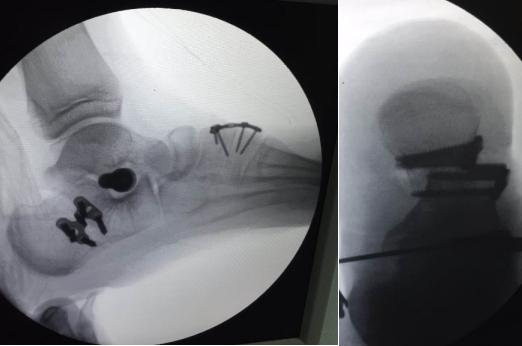

上图为患者扁平足术中影像资料